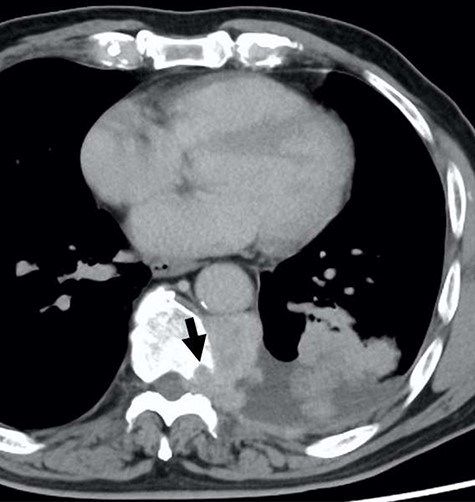

Since the disease progression might cause paresis, paralysis and loss of bowel/bladder function, palliative thoracic radiotherapy was planned. He received 36 Gray palliative radiotherapy. Six weeks after radiotherapy, the tumor was effectively decreased in size (Fig. 4).

The computed tomographic findings after 6 weeks after radiotherapy.